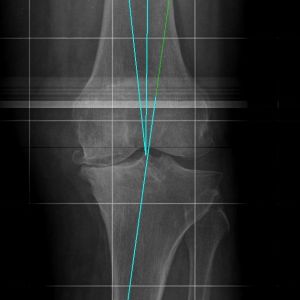

Deviazioni dell’asse anatomico del ginocchio in varismo o valgismo possono essere la causa predisponente allo sviluppo di una artrosi del ginocchio.

• Da esami strumentali che permettono di confermare l’ipotesi diagnostica, tra gli esami di fondamentale utilità ricordiamo la radiografia del ginocchio e la proiezione assiale di rotula.